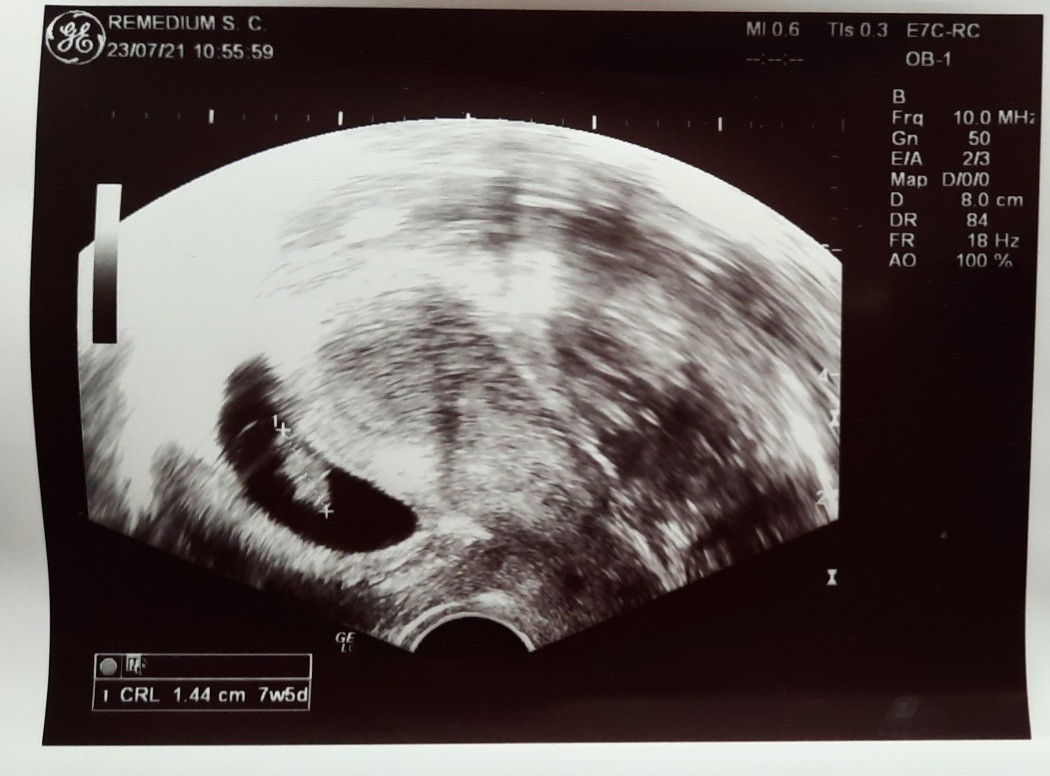

SuperJuż poserce bije. Wymiar 1.44cm, 7tydzien 5 dzień. Mam przyjść jak najszybciej z wynikami krwi. Dostała też skierowanie na prenaralne z nfz

Ale superJuż poserce bije. Wymiar 1.44cm, 7tydzien 5 dzień. Mam przyjść jak najszybciej z wynikami krwi. Dostała też skierowanie na prenaralne z nfz